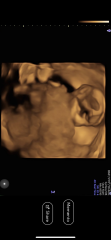

Im currently 16 weeks and 4 days pregnant and just had our gender scan and fetal well being check which went really well although baby wasn’t playing ball with getting a good picture, they’re face was facing my back so we could only see back of baby’s head mostly.

however after receiving the pictures the 3d/4d scan has absolutely terrified me and I wanted to see if this is normal at this stage! I appreciate they move a lot but it seems a chunk of their face is missing!

Terrified from 16 week sneak peek!